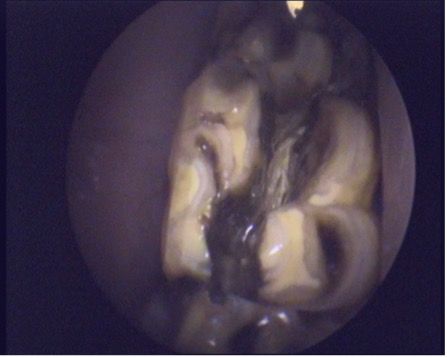

Fractures can be traumatic in origin, such as following a kick or a collision, or idiopathic. Although mandibular cheek teeth are more commonly involved in traumatic fractures, maxillary cheek teeth, especially the 09s, are frequently found to have idiopathic fractures. Lateral slab fractures through the 2 lateral (buccal) pulp cavities and midline sagittal fractures through both infundibula (Figure 2), believed to be predisposed by infundibular cemental hypoplasia (caries), are common fracture configurations for cheek teeth.6 Some uncomplicated crown fractures may not have pulpar involvement, but some more complicated fractures will. These can develop apical infection and, in some cases, secondary sinusitis, depending on the teeth involved. CT can help in determining the extent of the apical and sinus involvement and, therefore, putting in place a comprehensive treatment plan.7

The main treatment for a fractured tooth associated with periapical infection is extraction. This is typically performed orally but, in more complicated cases, can necessitate a minimally invasive buccotomy, where an incision is made through the mucosa for the insertion of specialized equipment to elevate and extract the affected tooth. Oral extraction involves elevating the mucosa surrounding the affected tooth, spreading the affected tooth from each adjacent tooth, and breaking the periodontal ligament using traction and a molar extractor.8